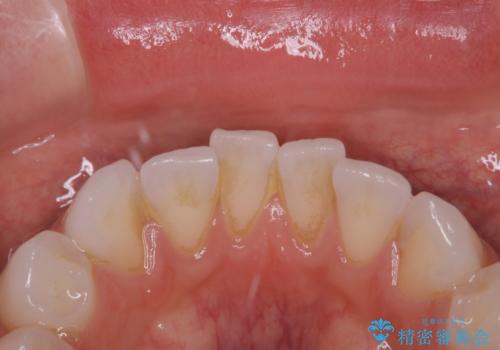

治療症例の内容

- 20代女性

- 1日

- しばらく歯科でのクリーニングをしていないため、きれいにしたいとのことでした。

PMTC30分コースを行いました。